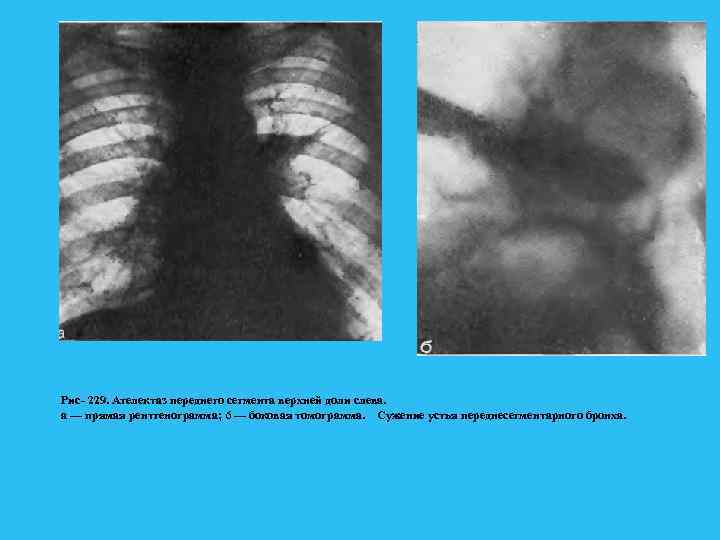

Рентгенологически проявлением этой стадии является сегментарное вздутие, которое развивается по мере дальнейшего роста опухоли и суже ния просвета бронха. Поскольку в фазе выдоха просвет бронха суживается, происходит накопление остаточного воздуха в сегменте и его прогрессирующее вздутие. Эта фаза нарушения бронхиальной проходимости лучше прослеживается в фазе максимального выдоха (рис. 228). Рис. 228. Обеднение сосудистого ри сунка в правом легком. Прямая рентгенограмма. а — фаза вдоха; б — фаза выдоха: вздутие правого легкого» смещение средостения влево.

Применение функциональных проб позволяет заметить смещение средостения в фазе выдоха в противоположную сторону. Анализ легочного рисунка в этой фазе показывает, что соответственно пораженным участкам заметно обеднение сосудистого рисунка из за веерообразного раздвигания сосудистых ветвей и уменьшения кровенаполнения, вследствие повышенного внутриальвеолярного давления. По мере роста опухоли наступает четвертая фаза. Последняя связана с полным перекрытием просвета бронха, чему способствует скопление в нем слизи, мокроты и крови. Все эти факторы рано или поздно приводят к III стадии нарушения бронхиальной проходимости, к возникновению ателектаза (рис. 229). Именно сложный характер пробки, обтурирующей бронх, является одной из причин так называемых перемежающихся ателектазов. Стадия ателектаза обычно диагностируется при поражении зональных и долевых бронхов и реже при сегментарных. Сегментарные поражения часто расцениваются как проявления пневмонии, и лишь тогда, когда развивается ателектаз зоны или доли, устанавливается диагноз рака легкого. Описанные фазы нарушения бронхиальной проходимости от гиповентиляции через клапанное вздутие к ателектазу также последовательно наступают и при развитии опухоли в зональных долевых и главных бронхах.

Рис 229. Ателектаз переднего сегмента верхней доли слева. а — прямая рентгенограмма; 6 — боковая томограмма. Сужение устья переднесегментарного бронха.